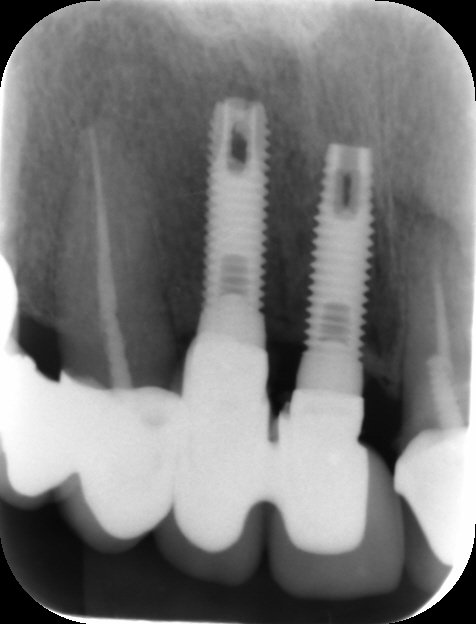

Buenas tardes! Me podéis ayudar con la marca de este implante porfavor?

Acude un paciente con un implante puesto hace unos meses, no sabiendo que tipo de implante es. Necesito saberlo para la elaboración de la corona.

Un amigo dentista me pide rehabilitar un paciente que le colocaron estos implantes en el oeste de Los Ángeles en 2017 ya que el paciente no puede regresar a EU. [...]